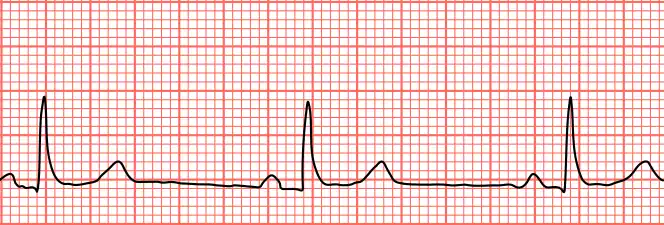

Sinus bradycardia seen in lead II with a heart rate of about 50BPM

Bradycardia is defined as a heart rate of under 60 beats per minute (BPM) in adults, though symptoms generally only result when the heart rate is under 50.[1] Mild symptoms may include tiredness and shortness of breath with exercise.[2][5] Severe symptoms may include confusion, chest pain, syncope, and heart failure.[1]